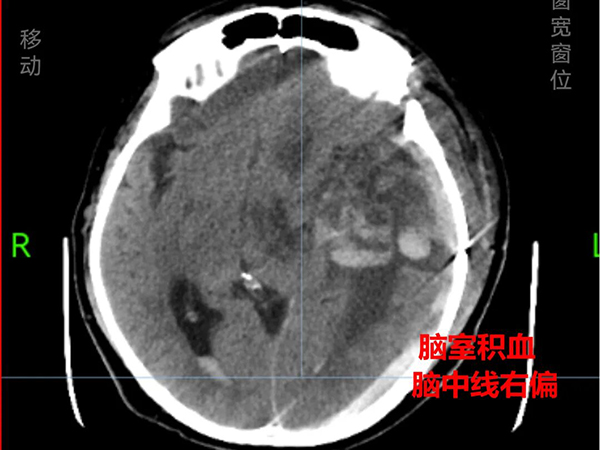

入院时,小周气管、胃管、尿管多重插管,病情复杂危重,不容乐观——呼吸心跳骤停后,虽经3分钟紧急复苏成功,但生命体征不稳,仍处于深度昏迷状态,对光反应迟钝,多项检验指标异常,影像结果提示左侧额颞叶多灶性脑出血,蛛网膜下腔少许出血,颞枕部硬膜下血肿,脑室系统积血,脑中线右偏,双肺坠积改变,还伴有中枢性呼吸衰竭、电解质紊乱和低蛋白血症,预后不佳。

神经内科、神经外科与康复医学科接过救治的“接力棒”:一方面,予以脑保护、抗感染、抗癫痫、止咳化痰、营养支持等对症治疗;另一方面,采取渐进式呼吸肌训练、咳嗽排痰训练、肢体锻炼等综合训练。经过1个多月的系统治疗与精心护理,小周顺利拔除了气管插管和尿管,恢复了自主呼吸和言语功能,复查显示其颅内积血已基本吸收,脑中线复位,肺部感染也得到有效控制,并于1月28日顺利出院。